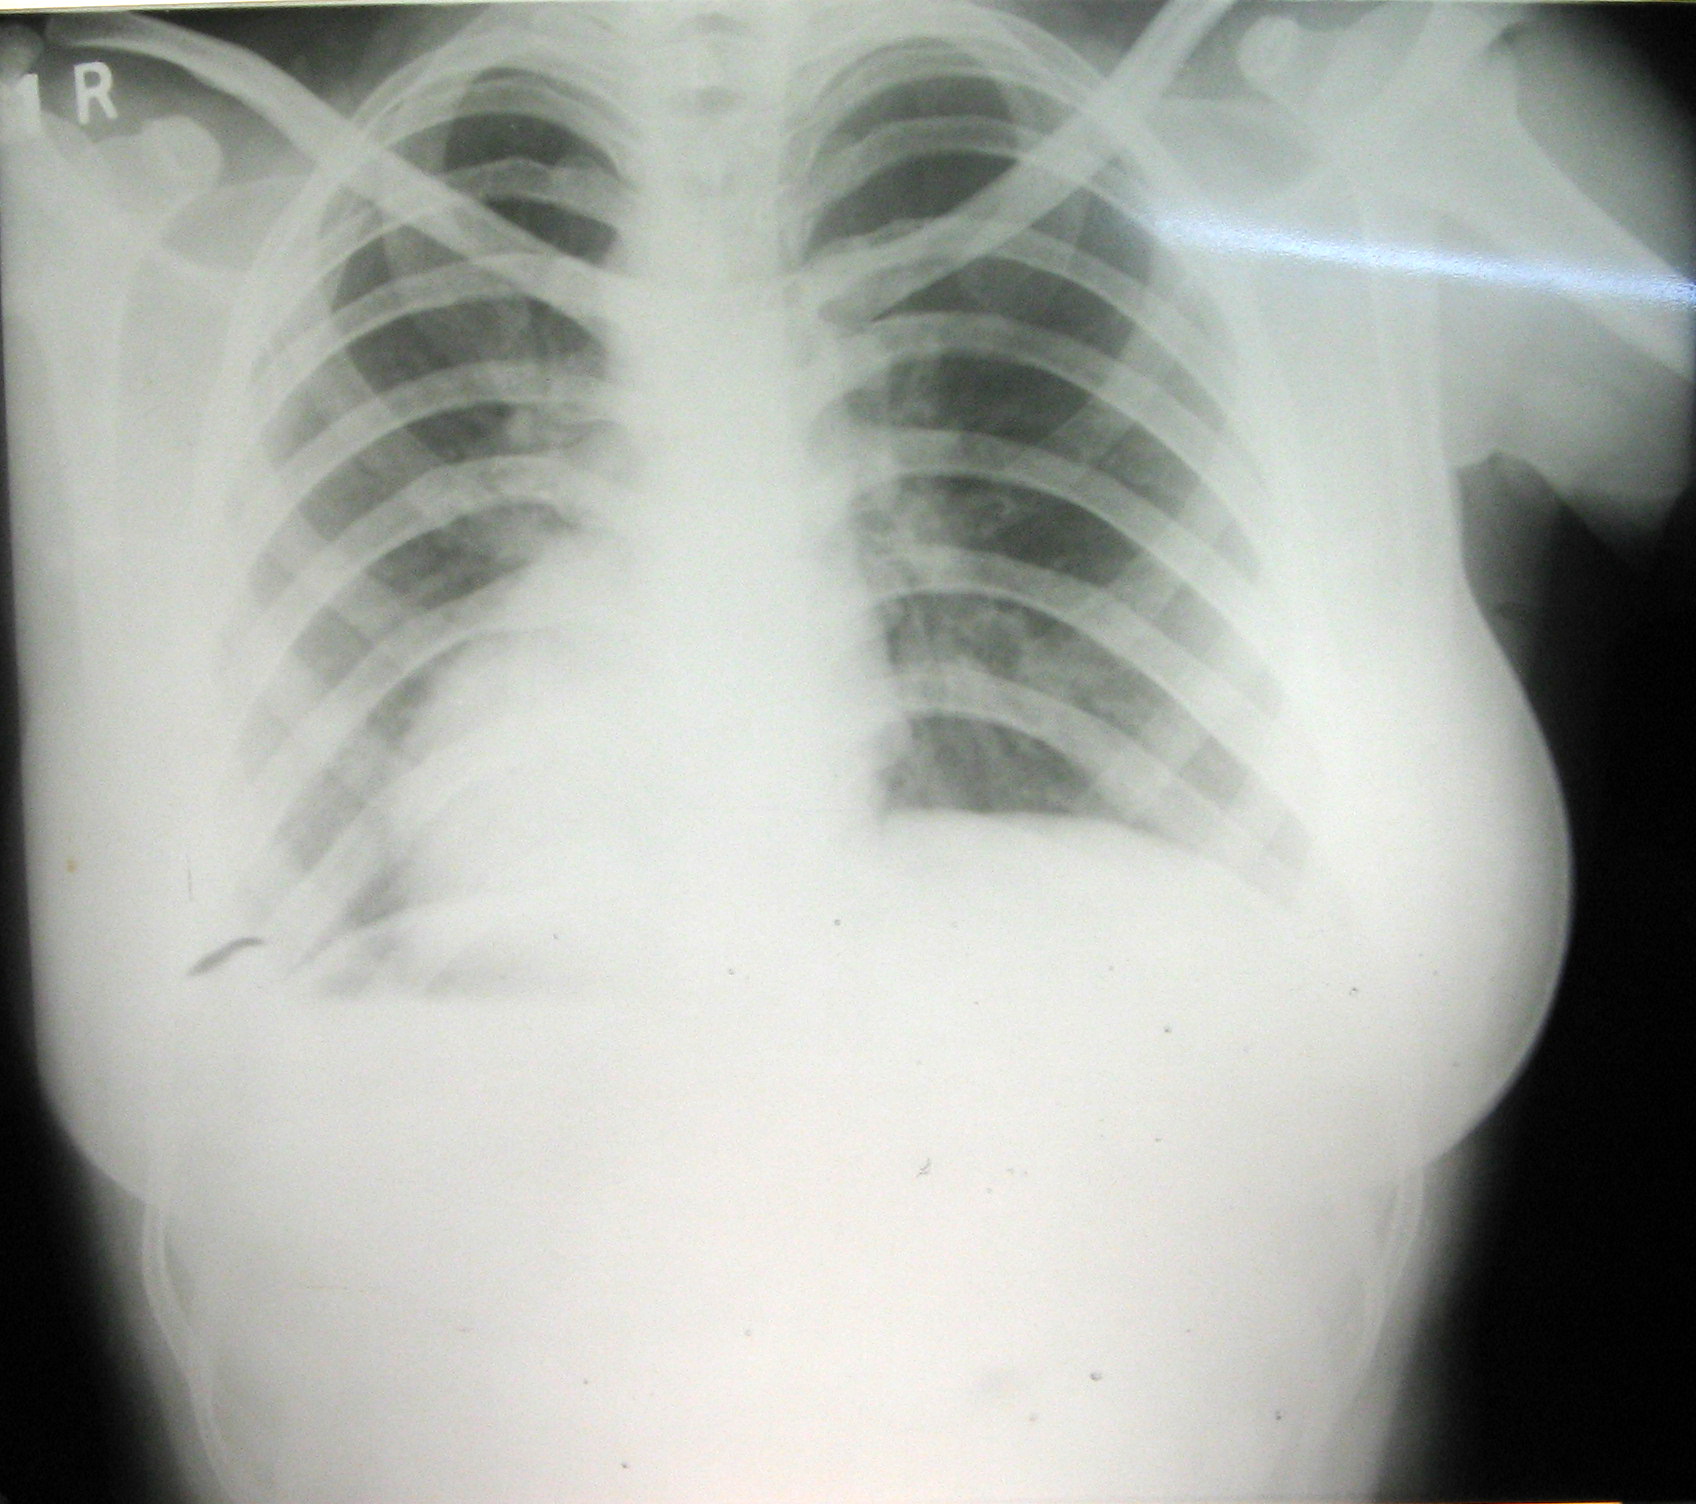

Декстрокардия

Декстрокардия 116 фото